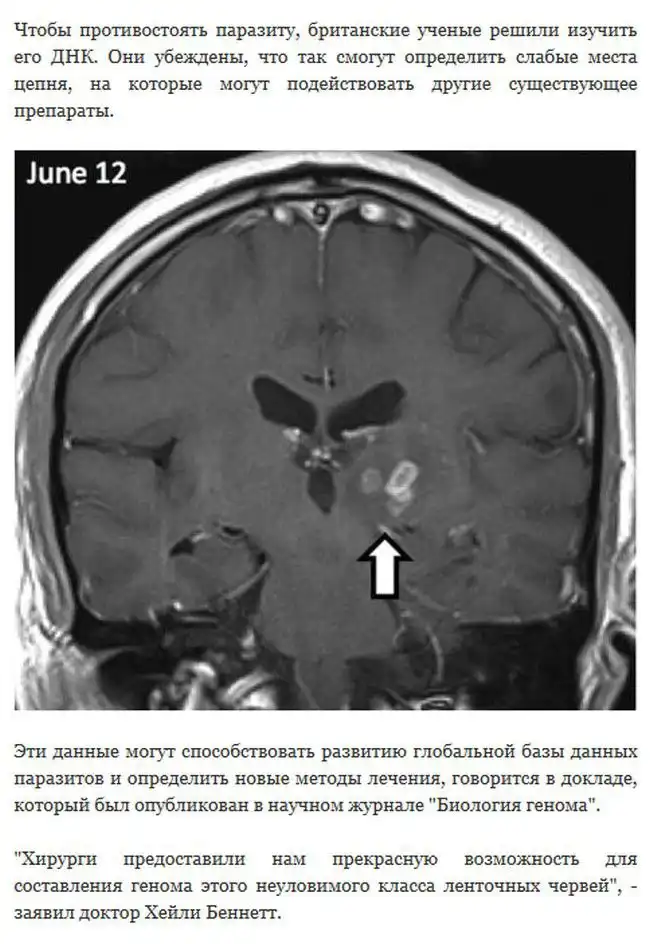

В Великобритании исследования одного пациента показали, что живущий в его мозге червь смог преодолеть расстояние в 5 сантиметров, от правого края до центра. Для того, чтобы продвинуться на такое расстояние, сантиметровому цепню понадобилось целых четыре года.